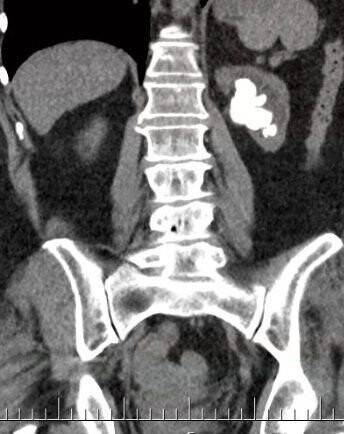

Çanakkale'nin Çan ilçesinde yaşayan Nesibe Işık, 5 gün önce ÇOMÜ Hastanesi Üroloji Bölümü'ne böbrek ağrısı şikayetiyle başvurdu. Nesibe Işık'ın yapılan tetkik ve kontrollerinde böbreğinde büyük bir taş parçası olduğu tespit edildi. Ameliyata karar verildi. Üroloji Bölümü'nden Doç. Dr. Eyüp Burak Sancak ve ekibi tarafından Çanakkale'de ilk kez uygulanan "Miniperk" yöntemiyle Nesibe Işık ameliyat oldu. Işık'ın böbreğini kaplayan taş, parçalandı. Yaklaşık yüz parçaya ayrılan taş parçaları, böbrekte küçük bir delik açılarak alındı.

Nesibe Işık'ın sol böbreğinde böbreğin içerisini tamamen dolduran, bilimsel olarak geyik boynuzu olarak adlandırılan dev böbrek taşı mevcut olduğunu belirten Doç. Dr. Eyüp Burak Sancak, "Hastamızın böbrek fonksiyonları da sınırda çalışmaktaydı. Bu nedenle hastamıza ve böbreğe daha az hasar verecek, Çanakkale'de ilk kez uygulanan "Miniperk" yöntemi ile daha küçük bir delikten böbrek taşlarının tamamını temizledik. Günümüzde teknolojik gelişmeler ve bilimsel yöntemler hep daha az zarar veren, daha küçük kesi ile yapılan cerrahilere doğru değişim göstermekte, biz de ÇOMÜ Hastanesi Üroloji Anabilim Dalı olarak, bu teknolojiye ayak uydurma çabasındayız. Hastalara daha az hasar veren "Minimal Invaziv" olarak adlandırılan yöntemleri uygulamaya çalışıyoruz. Bu nedenle hastamıza çok daha küçük bir delikten, çok büyük olan böbrek taşı alma işlemini yani, ilk kez "Miniperk" yöntemini uyguladık. Hastamızın şu an sağlık durumu gayet iyi, çok kısa zamanda toparlandı" dedi.